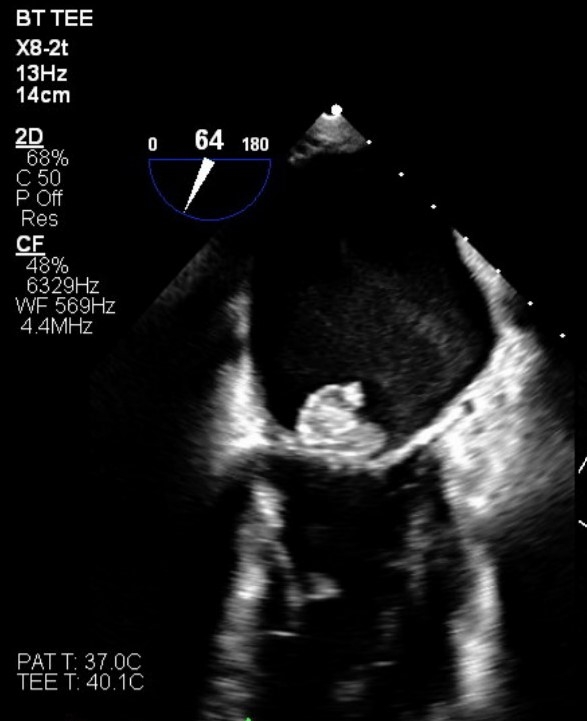

The patient was stabilized and transferred to the general medicine ward. He remained encephalopathic with persistent leukocytosis, raising concern for occult untreated infection. A detailed physical examination revealed midline thoracic and lumbar spine tenderness and a swollen right wrist and hand. MRI imaging confirmed T8-T9 and L3-L4 discitis-osteomyelitis with spinal epidural abscesses, as well as right wrist septic arthritis. Given concern for septic emboli being the source of multifocal infection, further evaluation with transesophageal echocardiogram (TEE) was performed; this revealed a 1.4 x 1.6 cm vegetation on the posterior mitral leaflet, without significant regurgitation or stenosis.